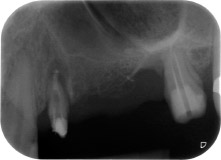

Mujer de 58 años de edad, que además es una apreciada colega y amiga, y se quejaba de dolor y de un aumento en la movilidad del pilar del puente de la pieza dental 24. También había inflamación periodontal, con bolsas de una profundidad de 7 mm en sentido mesiobucal y más de 12 mm en sentido distal, así como furcación de tercer grado. Asimismo, la radiografía reveló una lesión periodontal extensa alrededor de la región apical de la pieza dental 24 (figura 1) tratada previamente con endodoncia (alio loco).

En la raíz bucal, faltaba todo el hueso vestibular y distal. Básicamente, la fijación se limitó a la raíz palatal, lo que corroboró el mal pronóstico preliminar. La pieza 27 también mostró una fijación horizontal reducida (figura 12) y una rarefacción apical mínima (figura 1), si bien sin síntomas clínicos.